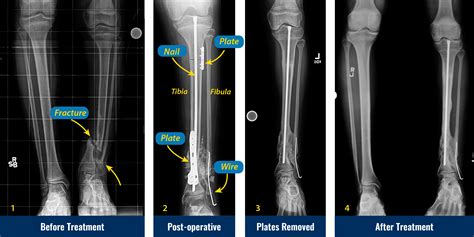

Okay, let’s talk about treatment options for tibial pseudoarthrosis . The goal here is to get that bone to heal properly and restore stability to your leg. There are both non-surgical and surgical approaches, and the best option depends on the specific situation. Non-surgical treatments are typically considered for milder cases or when surgery isn’t an option. This might involve using a cast or brace to provide stability and support to the fracture site. Physical therapy can also be helpful to strengthen the surrounding muscles and improve function. However, non-surgical treatments are often not enough to achieve complete healing. Surgical treatments are usually necessary for more severe cases of pseudoarthrosis. One common procedure is bone grafting , where new bone is taken from another part of your body (usually the hip) or from a donor and transplanted to the fracture site. This provides a scaffold for new bone to grow on and stimulates the healing process. Another option is internal fixation , where metal plates, screws, or rods are used to stabilize the bone fragments. This helps to keep the bones in the correct position and promotes healing. In some cases, a combination of bone grafting and internal fixation is used. Another surgical technique involves the use of external fixation , where a frame is placed outside the leg and connected to the bone with pins or wires. This can provide stability and allow for gradual correction of any deformities. Electrical stimulation is another treatment option that can be used to promote bone healing. This involves applying a small electrical current to the fracture site, which can stimulate bone cells and accelerate the healing process. The choice of treatment depends on several factors, including the size and location of the pseudoarthrosis, the patient’s overall health, and the presence of any other medical conditions. A thorough evaluation by an orthopedic surgeon is essential to determine the best course of action. The surgeon will consider all of these factors and discuss the risks and benefits of each treatment option with the patient. In addition to the specific treatments mentioned above, it’s also important to address any underlying factors that may be contributing to the pseudoarthrosis, such as infection, poor blood supply, or medical conditions. Addressing these factors can improve the chances of successful healing. After surgery, rehabilitation is crucial to regain strength, flexibility, and function in the leg. This typically involves a structured program of physical therapy exercises, which may include range of motion exercises, strengthening exercises, and weight-bearing exercises. The rehabilitation process can take several months, but with dedication and hard work, most patients are able to return to their normal activities. Remember, the goal of treatment is to achieve a stable and functional union of the bone, so that you can get back to doing the things you love. With the right treatment and rehabilitation, most patients with tibial pseudoarthrosis can achieve a successful outcome.